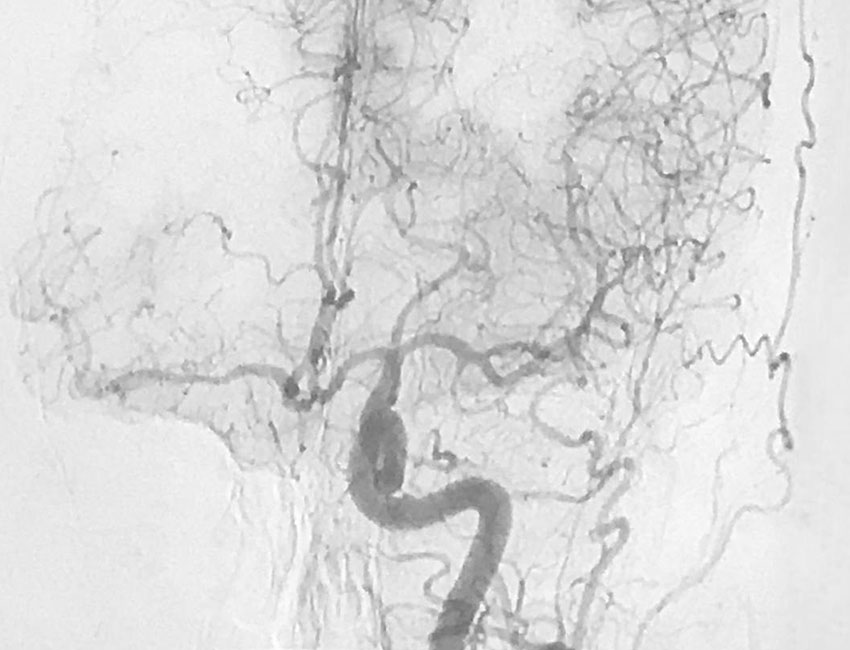

Η διάγνωση της καρωτιδικής νόσου γίνεται μέσω έγχρωμης υπερηχογραφίας (triplex) των καρωτίδων. Ακολουθεί CTA ( αξονική αγγειογραφία ) αγγείων τραχήλου – εγκεφάλου για προσδιορισμό της έκτασης της αθηρωματικής πλάκας και ανατομίας της περιοχής.